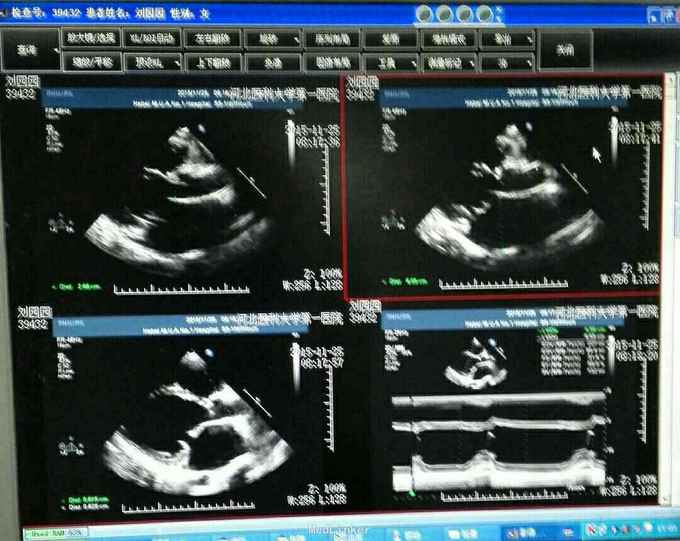

查体 生命体征平稳,口唇无发绀,双肺呼吸音清,未闻及干湿性罗音,心律不齐,于心尖处可闻及3/6级收缩期杂音,肺动脉瓣第二心音亢进,腹部平软无压痛反跳痛,肝脾肋下未闻及肿大。 辅助检查 心脏彩超 先天性心脏病 室间隔缺损修补术后 三尖瓣赘生物形成,三尖瓣反流 二尖瓣反流。 胸片示 全心增大 肺部瘀血。

诊断先天性心脏病 室间隔缺损修补术后 三尖瓣赘生物形成 三尖瓣反流 二尖瓣反流 治疗 患者入院后完善各项术前检查及准备在全麻体外循环下行二尖瓣置换术 三尖瓣置换术 手术过程 患者取平卧位于手术台,常规消毒铺单,摇摆钜开胸骨进胸,小心分离胸骨下粘连组织,心外探查 全心增大,右心房及左心房重度增大,常规建立体外循环,阻断升主动脉冷灌心脏停跳,切开右心房放置左心引流,切除病变的二尖瓣及三尖瓣以机械瓣膜置换之,开放升主动脉,除颤心脏复跳,辅助循环,生命体征稳定后,减量停机,撤除体外循环管道,彻底止血关胸,患者安反监护室。